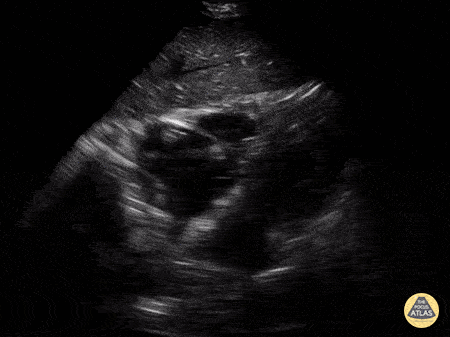

Acute PE clot in RA Samantha King

View: Unspecified Parasternal Long Axis Parasternal Short Axis Apical Four-Chamber Subcostal Four-Chamber Subcostal Inferior Vena Cava Right Upper Quadrant Left Upper Quadrant Suprapubic Longitudinal Suprapubic Transverse Subxiphoid Anterior Thoracic Phrenic